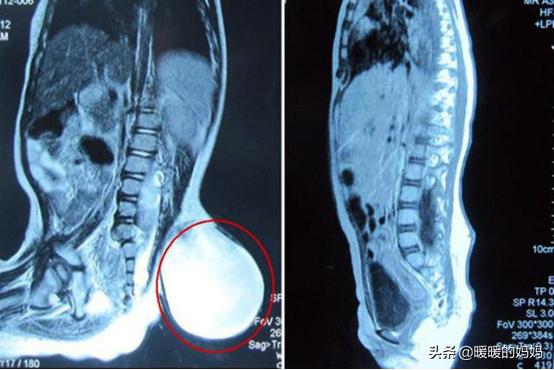

原来宝宝后来长出的“尾巴”是一种非常严重的疾病 , 是由于宝宝先天性发育不良而导致的 , 在经过一番细致的检查后 , 医生发现宝宝的小尾巴不仅向外不断的生长 , 内里也是不断的生长 , 甚至已经和他的脊椎产生接触 , 如果不尽快治疗 , 很有可能会导致孩子的后半生出现行走上的困难 , 在听到医生的结论之后 , 小郭非常害怕 , 在平常的生活中孩子也没有什么异样 , 怎么会得这样的病呢?